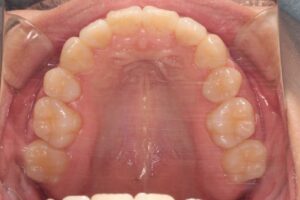

上顎両側側切歯が舌側転位していて、両側犬歯が八重歯になっています。また、本症例で特徴的なのは下顎の両側第二大臼歯が傾斜していて半埋伏状態にあることでした(治療前レントゲンの赤い丸で囲った部分)。ほぼ水平埋伏状態で一見すると親知らずかと思うほどです。さらにはその後方には第三大臼歯も水平埋伏しています。難易度は高いなと感じましたがとにかく第二大臼歯を整直(アップライトともいいます)して利用する以外に選択肢はないので叢生の改善と第二大臼歯の整直を治療目標としました。

上顎の叢生改善のスペース獲得のために上顎の第一小臼歯を抜歯、下顎に関しては凸凹は軽度ですが第二大臼歯整直のためのスペースを全て後方に求めるのは無理なので、前方にスペースを確保する目的で両側の第二小臼歯を抜歯しました。また、矯正治療前に下顎両側第三大臼歯も抜歯しました。

治療中の下顎歯列の写真は第二大臼歯に装置を装着して第二大臼歯を整直し始めたところです。